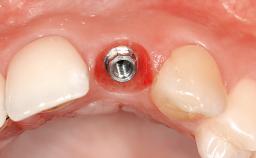

Replacement of an Upper Right Central Incisor with a Regular Neck Implant, Restored with (1) an All-Ceramic Crown, Transocclusally Screw-Retained, and (2) an Auro-Galvano Crown, Cemented, Seated on CAD/CAM Custom Mesostructures (ZrO2 and Titanium)

In February 2005, a 25-year-old female patient, a nonsmoker, was referred to our clinic due to tooth 11 presenting a chronic fistula following unsuccessful root-canal treatment and several attempts at endodontic surgery. The dental history revealed that more than ten years earlier, teeth 11 and 21 had been traumatized during a sports accident. Consequently, 11 had lost its vitality, and there were two moderate fractures of the mesioincisal borders of the two central incisors that had been restored with direct composite restorations. At the time of examination, the composite restorations showed signs of wear, some discoloration, and marginal infiltration. The patient also complained about a moderate discoloration of the clinical crown of the non-vital tooth 11. The patient was in good general health, and her medical history revealed no significant findings.